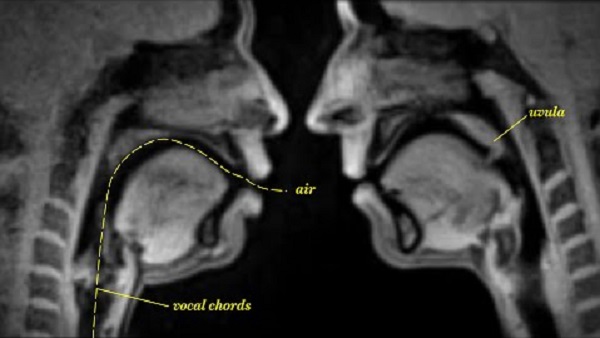

Na rozdiel od CT a RTG, MRI používa žiadne nebezpečné vyžarovanie. Konkrétnejšie, axiálne skenery používajú silné magnetické pole a strukoviny rádiových vĺn manipulovať protóny vodíka v ľudskom tele. Keď zdroj RF je zakázaný, protóny vodíka apokalytoyn ich postavenie vyžiarením energie, ktorá je zachytená a konvertujú na obrázky. MRI sú vo všeobecnosti drahšie a trvajú dlhšie ako CT vyšetrenia, ale poskytnúť podrobnejšie informácie. V tomto videu pár pôsobivé snímky MRI ľudského tela v akcii.